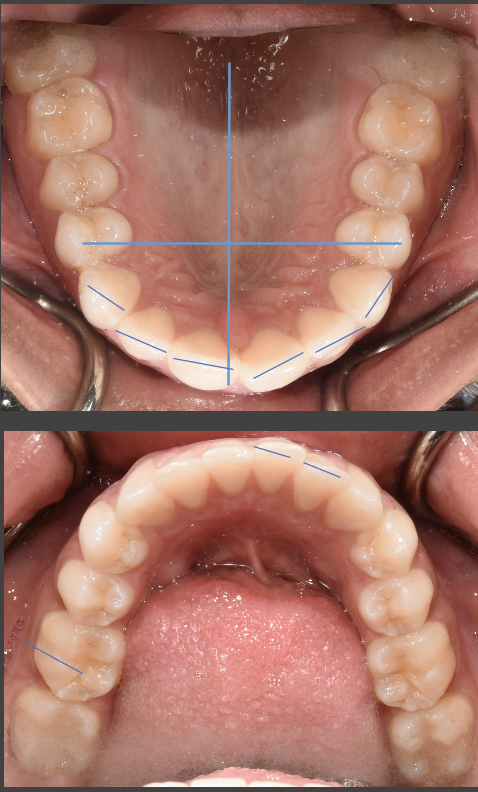

I found a "holistic" dentist a bit further away and considering how badly unaligned my bottom front teeth were alone they could just about close the gap with braces (I opted for Invisalign since it's quicker, convinient, better customization and end cost was about the same). They also drilled into the gums near the beginning to alegedly help with tooth movement.

So far at 18 weeks in the gap is half closed already at my age (37, odler you are the slower the bone movement rate apparently) and my bottom front row teeth and already perfectly aligned, not perfectly centered yet though it's getting there.

I still have another 25 ish weeks to go to fix my terrible underbite/overbite problems on both sides, also going for another gum drilling today actually, but this is more than possible, just expensive lol.